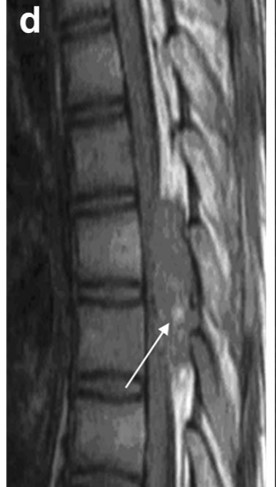

14歳男性:下肢の筋力低下

• CT

• T2WI

• T1WI

• Gd-T1WI